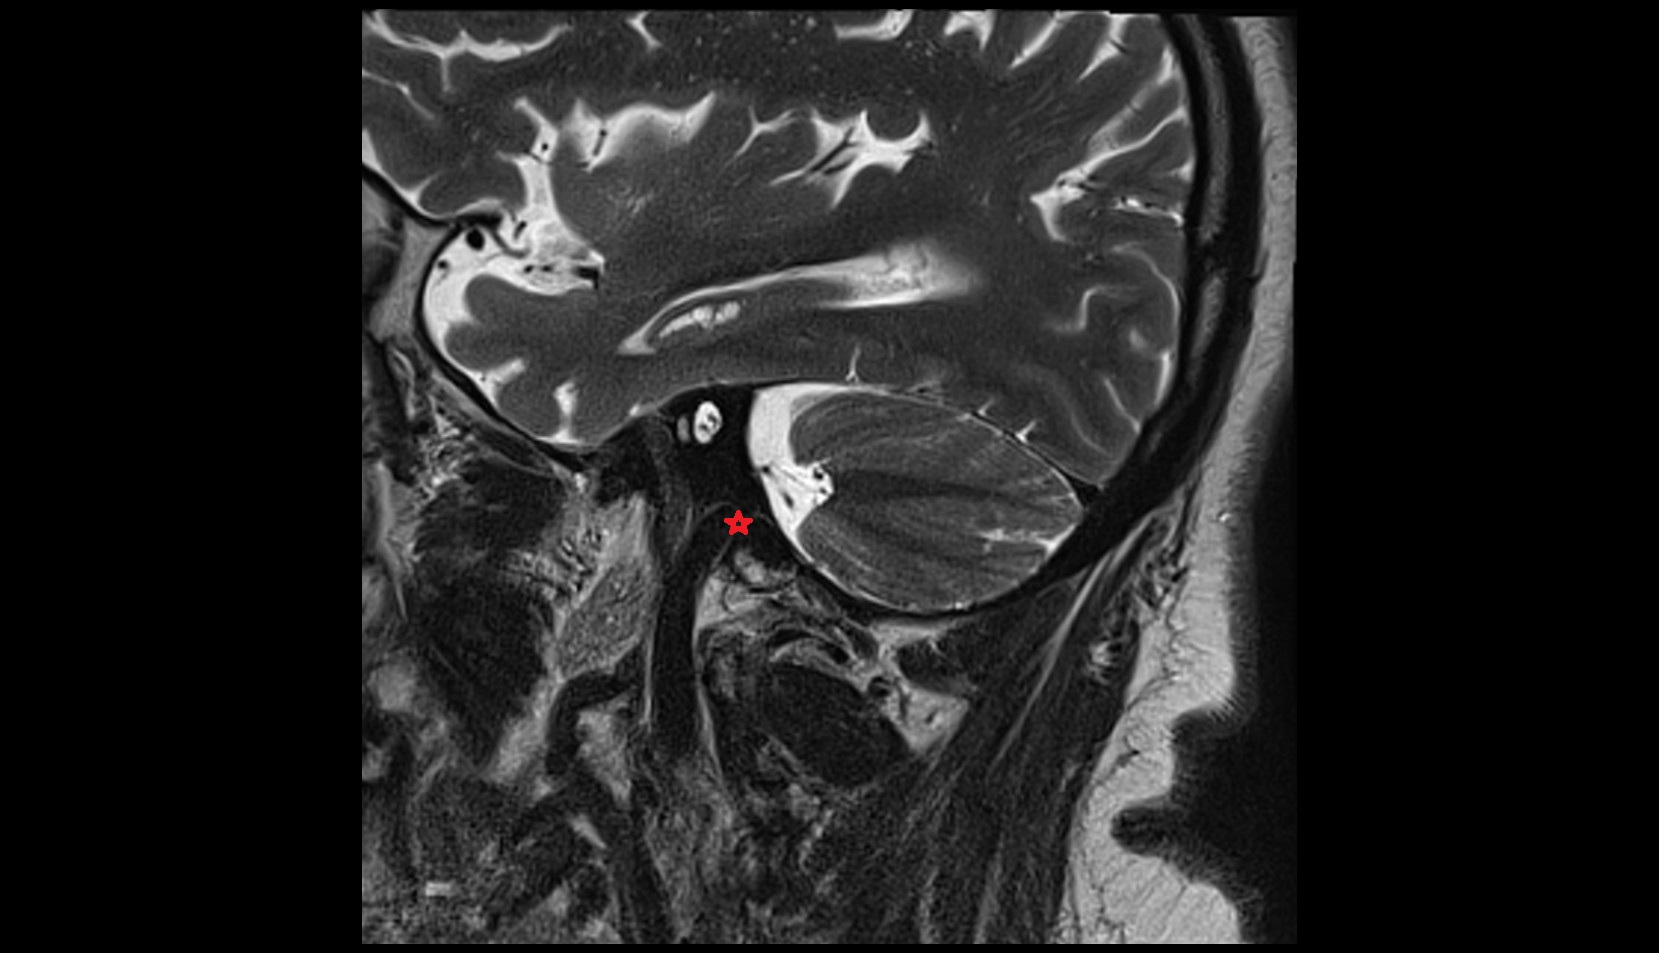

- Pituitary stalk

- Pituitary gland

- Anterior lobe of pituitary gland

- Posterior lobe pituitary gland